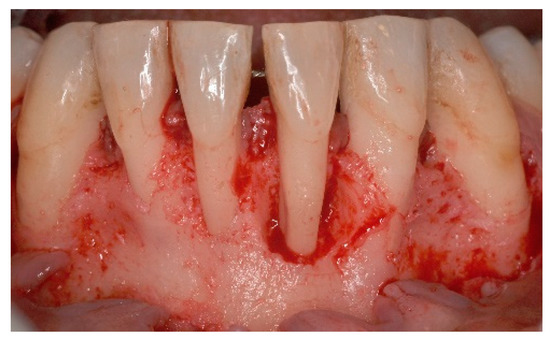

5. Materials and Methods